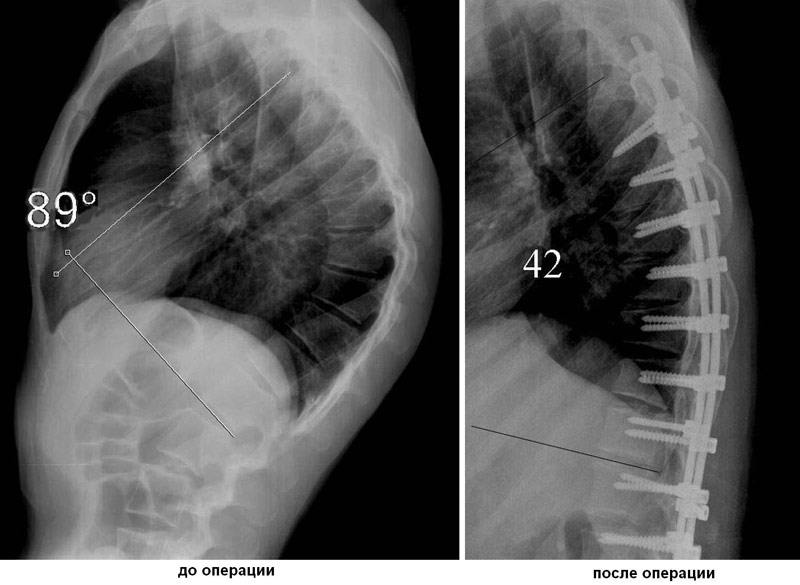

Показаниями к хирургическим вмешательствам при болезни Шейермана-Мау являются угол кифоза более 75 градусов, стойкие боли, нарушение работы органов дыхания и кровообращения. В ходе операции в позвонки имплантируются металлические конструкции (винты, крючки), позволяющие выравнивать позвоночник при помощи специальных стержней.